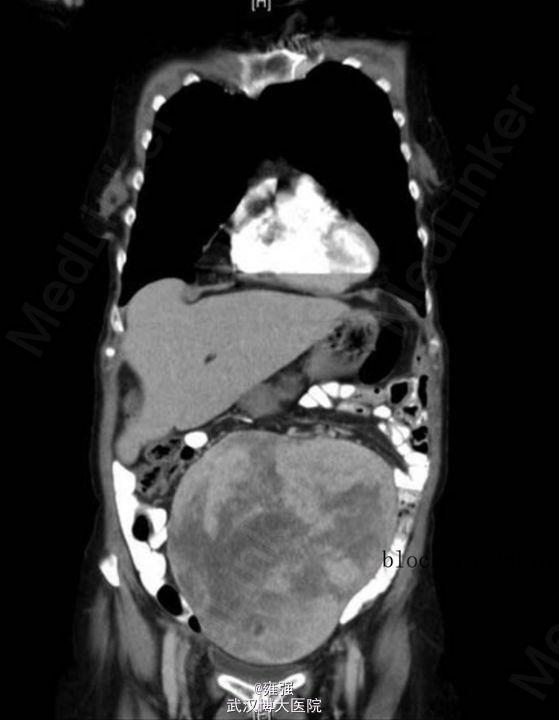

辅检:肿瘤标记物(CEA、CA19-9、CA125)均在正常范围,入院后腹部X片示下腹部出现增强的不透光区(如下图示)。术前TAP分段CT示盆腔内大型、界限清楚、中线测量为 18.8 cm×13.3 cm×18.2 cm、混合衰减的包块(如下图示),位于子宫前、膀胱之上,独立于子宫存在,考虑为起源于卵巢。